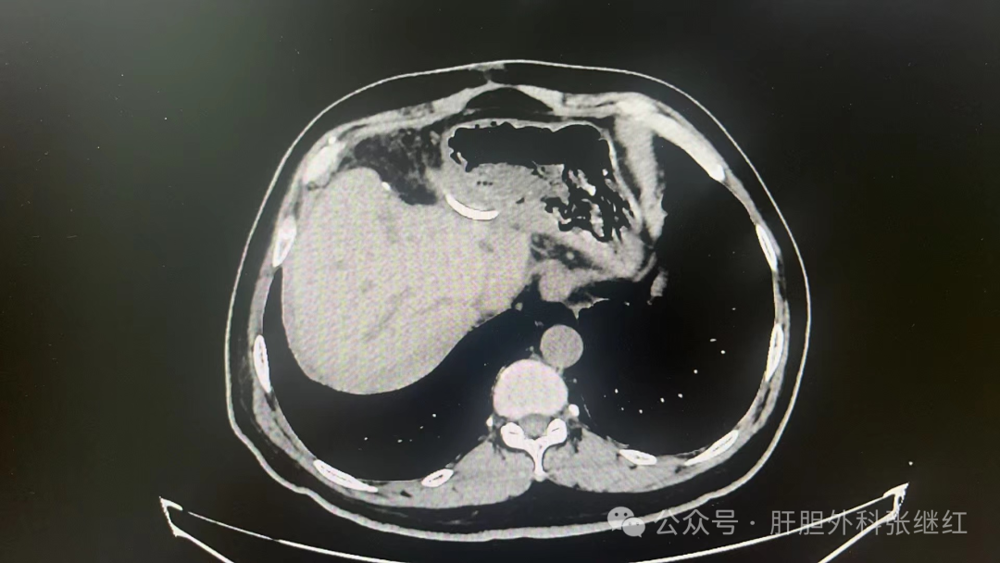

该患者是佛山复星禅诚医院肝胆胰外科病例,张继红医生有幸参加了术前多学科会诊和手术。1年前,一男性56岁病人,经CT、MR等影像学检查和病理活检确诊为胆管细胞癌,瘤体巨大,长径超过10厘米,且伴门静脉左支癌栓形成和多发腹腔淋巴结转移,经多学科会诊后决定应用吉西他滨和奥沙利铂化疗联合PD-L1单抗(度伐利尤单抗)免疫治疗进行转化治疗后再手术切除。经上述化疗联合免疫治疗五个疗程(每次均为单次给药,间隔时间21天)治疗后肿瘤明显缩小,直径约5厘米,淋巴结病灶也有所减少或缩小,达到了影像学部分缓解和手术切除的标准,经多学科会诊后决定行扩大左半肝切除及区域淋巴结清扫术,术后再行辅助治疗。本为腹腔镜手术,术中见左肝肿瘤萎缩明显,肿瘤压迫右侧肝蒂,肝门部及肝总动脉周围未见明显肿大淋巴结,肝门部粘连严重,仅清扫12a、12b、7-9组淋巴结所在区域脂肪淋巴组织,解剖离断左肝动脉、门静脉左支及左肝管,发现肿瘤基本位于缺血范围内,超声引导下在缺血线和S5段肿瘤外侧画切肝线,拟切除包括胆囊的S5段和左半肝,15+5min模式间歇性阻断肝门,沿预切线离断肝实质,达右肝蒂时发现肿瘤紧贴右肝蒂,为避免右肝蒂损伤,中转开腹完成整块切除包括胆囊的S5段及左半肝。手术后病理证实肿瘤100%坏死,清扫淋巴结亦未发现肿瘤细胞,达到病理学完全缓解(pCR)。术后早期肝断面少许积液,经引流后积液消失。目前病人状态良好,已无瘤生存半年余。

转化治疗前CT